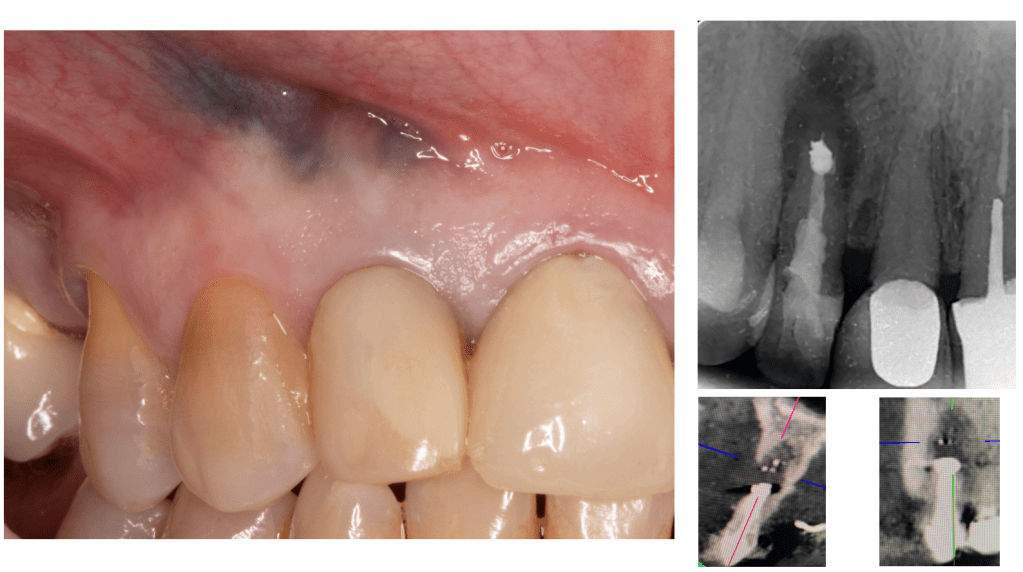

Cirugía canino puente

Descompresión por gran lesión